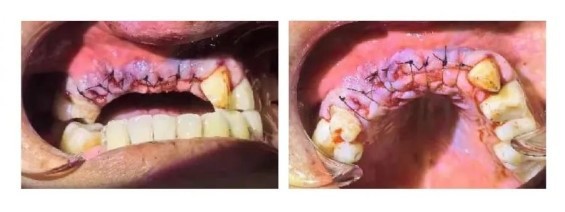

Aligning and suturing the gingiva and shaping the gingival papilla with nylon thread.